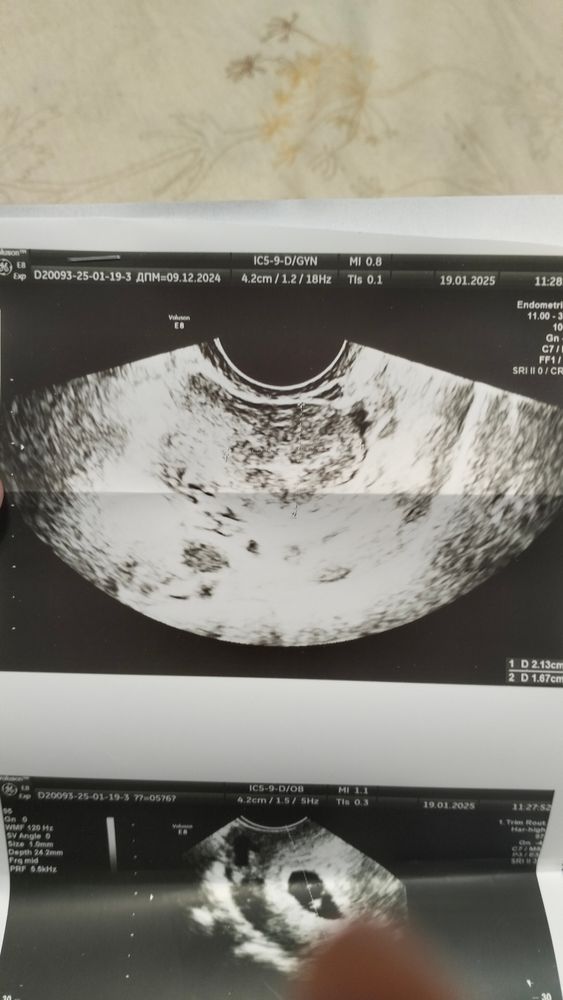

Здравствуйте! Была на УЗИ . Почти 6 недель. И врач сказала,что похоже на двойню,начала показывать,а я то ничего не вижу и не понимаю. Сказала придти через 2 недели повторно. Посмотрите, пожалуйста, может она ошиблась?

Похоже. Но ответ вам даст только узи в динамики.

Я, конечно, тоже не разбираюсь, но похоже на 2 колечка 😉🤗